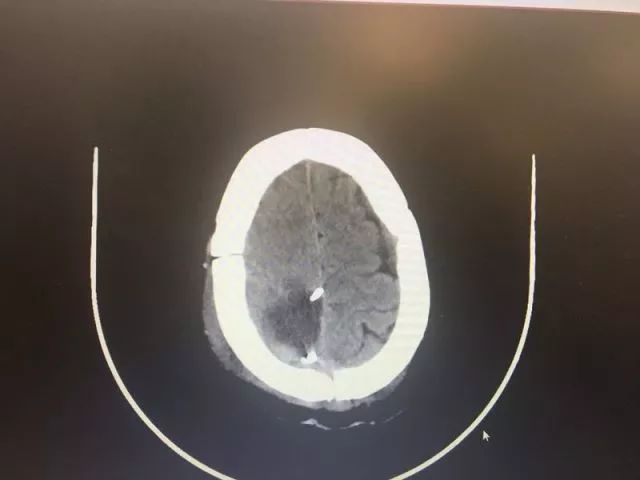

▲ 术后CT

5月15日,小鹿被推进了手术室。对于小鹿脑血管畸形团周围"寸土寸金"的脑组织,医生们下刀颇为仔细,尽可能把损伤降到最低,并且对附近非常重要的引流静脉做了妥善保护,还发现并处理了畸形团供血动脉上的动脉瘤,终于,在两个半小时后,一个直径为4公分左右的脑血管畸形团被成功剥离切除。